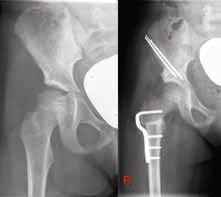

Salter-Beckenosteotomie

Dabei handelt sich um eine transversale Osteotomie oberhalb der Spina iliaca anterior inferior bis zum Foramen ischiadicum. Das Acetabulum kann im Anschluss nach ventrolateral geschwenkt werden. Das Drehzentrum hierbei liegt in der Symphyse. Die Osteotomie wird mittels K‑Drähten fixiert (Abb. 9). Der Eingriff eignet sich für Kinder zwischen dem 2. und 10. Lebensjahr 29. Dieses Verfahren sollte allerdings nicht zeitgleich an beiden Hüftgelenken durchgeführt werden.